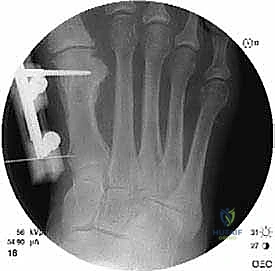

الخطوة الثالثة: قص العظم (Osteotomy)

باستخدام منشار جراحي ميكروسكوبي دقيق، يقوم الدكتور هطيف بقص عظم مشط القدم. تعتمد زاوية وشكل القص (مثل القص المائل أو القص على شكل حرف Z) على مقدار الإطالة المطلوبة وشكل العظم المتبقي من الجراحة السابقة.

الخطوة الرابعة: الإطالة والطعوم العظمية (Bone Grafting)

يتم إبعاد طرفي العظم المقصوص بلطف للوصول إلى الطول التشريحي المطلوب (والذي تم حسابه مسبقاً في صور الأشعة). لملء الفراغ الناتج عن الإطالة، يتم استخدام طعم عظمي (Bone Graft).

* الطعم الذاتي (Autograft): غالباً ما يتم أخذ قطعة صغيرة من العظم من كعب المريض (عظم العقب) أو من عظم الحوض، وهو الخيار الأفضل لأنه يحفز الالتئام السريع.

* الطعم الصناعي أو العظم البنكي (Allograft): يمكن استخدامه في بعض الحالات لتجنب إحداث جرح إضافي.

الخطوة الخامسة: التثبيت الداخلي القوي (Internal Fixation)

لضمان التئام العظم في وضعه الجديد والطويل، يجب تثبيته بقوة شديدة. يستخدم الدكتور هطيف أحدث الشرائح المعدنية التيتانيوم ذات الزاوية الثابتة (Locking Plates) والمسامير الدقيقة. هذا التثبيت القوي يمنع أي حركة بين العظام ويسمح ببدء العلاج الطبيعي في وقت مبكر.